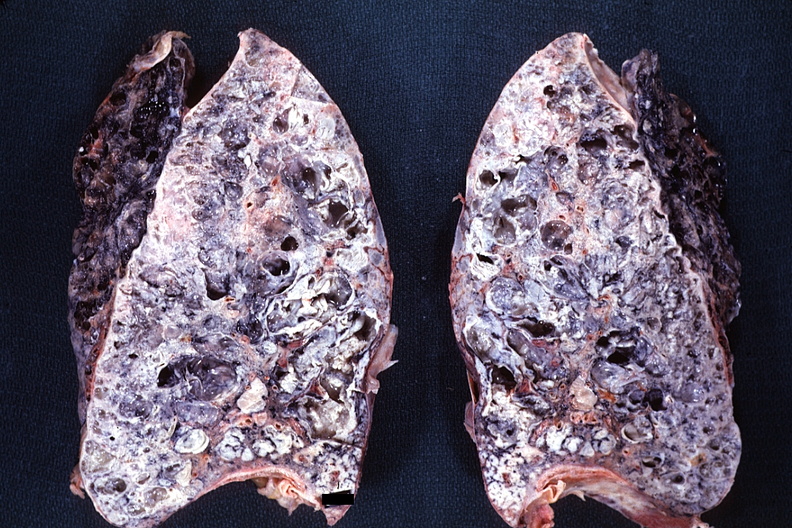

_重度肺纖維化的晚期